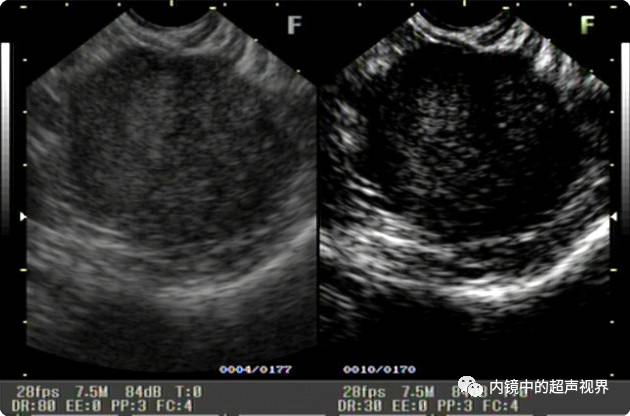

再来一张间质瘤的图片,也是DR30和80的对比。

有没人觉得,这个间质瘤的图片跟前面两个病灶不太一样,似乎感觉高DR模式看起来更舒服,那是因为,间质瘤为低回声,它周围的软组织为高回声,本身就能形成良好的对比,无需降低DR,而高DR模式更显细腻。

间质瘤